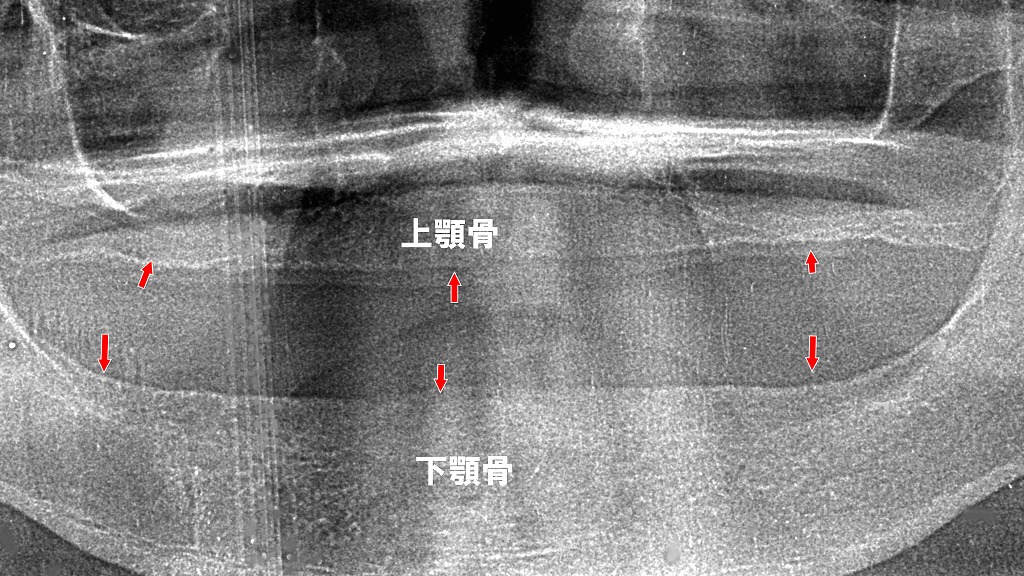

この画像は下顎の総入れ歯(総義歯)の粘膜面を撮影したものです。

🦷 画像の解説

- 義歯の構造

ピンク色のレジンで作られた下顎総義歯で、粘膜面(口腔内で顎堤に密着する面)が見えています。 - 歯槽骨吸収の影響

下顎では、歯を失って時間が経つと歯槽骨が吸収して平坦化しやすく、義歯の維持力(吸着力)が低下します。写真からも、中央部(オトガイ部)が浅く、顎堤が低い様子が推察されます。

⚠️ 想定される臨床的問題

- 外れやすい(維持不良)

下顎は上顎に比べて吸着面積が小さく、筋や舌の動きで浮き上がりやすいです。特に骨吸収が進んでいる場合は、義歯が安定しにくくなります。 - 吸着しない(陰圧不足)

底面がフラットで辺縁封鎖が不十分だと、陰圧が働かず、吸着力が得られません。粘膜面の精密印象が必要です。 - 痛みが出やすい(粘膜圧迫)

吸収した顎堤では粘膜が薄く、咬合圧が一点に集中しやすいため、咀嚼時や装着時に疼痛が出やすくなります。義歯床の調整やリライニング(裏打ち)で緩和が可能です。

💡 改善のための対応

- 精密印象による再製作(個人トレー+シリコン印象)

- リライニングによる適合性改善

- 吸着義歯(シリコーンリライナー、筋形成)で安定性向上

- インプラントオーバーデンチャーの検討(骨吸収が著しい場合)

赤矢印が示す部分は、総入れ歯を長期間使用することで起こる“顎の骨の吸収(骨が痩せる)”を示した像です。

歯がなくなると、噛む刺激が骨に伝わらず、上顎・下顎ともに徐々に骨量が減少していきます。

この骨吸収が進行すると、

- 入れ歯が安定しにくい

- 痛みやすい

- 嚙みにくい

- 見た目の変化(口元が痩ける)

といった問題が起こりやすくなります。

総入れ歯は、定期的な調整と顎骨の状態チェックがとても重要です。骨吸収が進む前に、適切なメンテナンスや治療選択肢(ミニインプラント併用など)を検討しましょう。